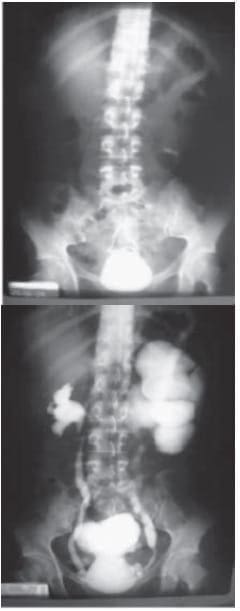

Urografía excretora: Litiasis Vesical e imagen de catéter doble J. Uretero-hidronefrosis izquierda. Reflujo V–U izq. G IV). Divertículo vesical.

Es llevada a cirugía donde se realiza nefroureterectomía izquierda más cistolitotomía sin complicaciones.

Hallazgos: Uretero-hidronefrosis izquierda, con múltiples adherencias peri renales e intestinales, catéter doble “J” y gran lito vesical. Uréter derecho de aspecto normal.